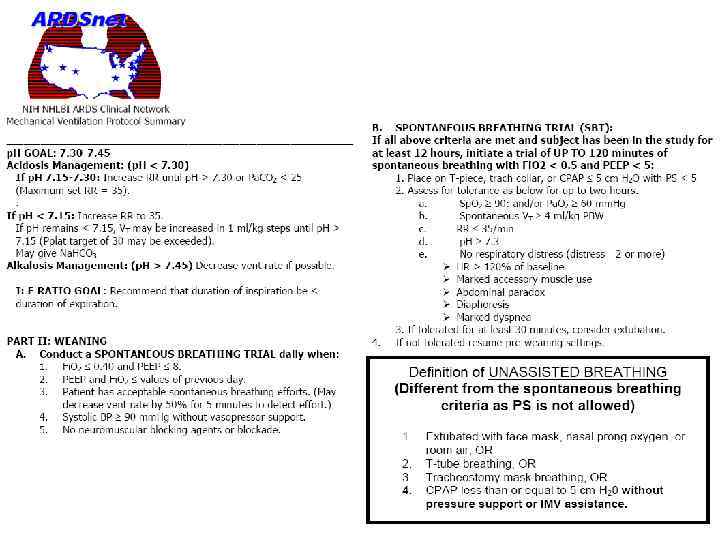

Мета-анализ (2010) трёх больших исследований, включавших 2299 пациентов - ALVEOLI (2004), LOVS (2008), EXPRESS (2008) • Пациенты исходно сравнимых групп получали РЕЕР около 8 -9 (Н, 1163) или около 11 -15 см (В, 1136) • Отношение шансов выживания при ОРДС В/Н = 0, 90 (95% ДИ 0, 81— 1, 00, Р=0, 049) •

Мета-анализ (2010) трёх больших исследований, включавших 2299 пациентов - ALVEOLI (2004), LOVS (2008), EXPRESS (2008) • Пациенты исходно сравнимых групп получали РЕЕР около 8 -9 (Н, 1163) или около 11 -15 см (В, 1136) • Отношение шансов выживания при ОРДС В/Н = 0, 90 (95% ДИ 0, 81— 1, 00, Р=0, 049) •